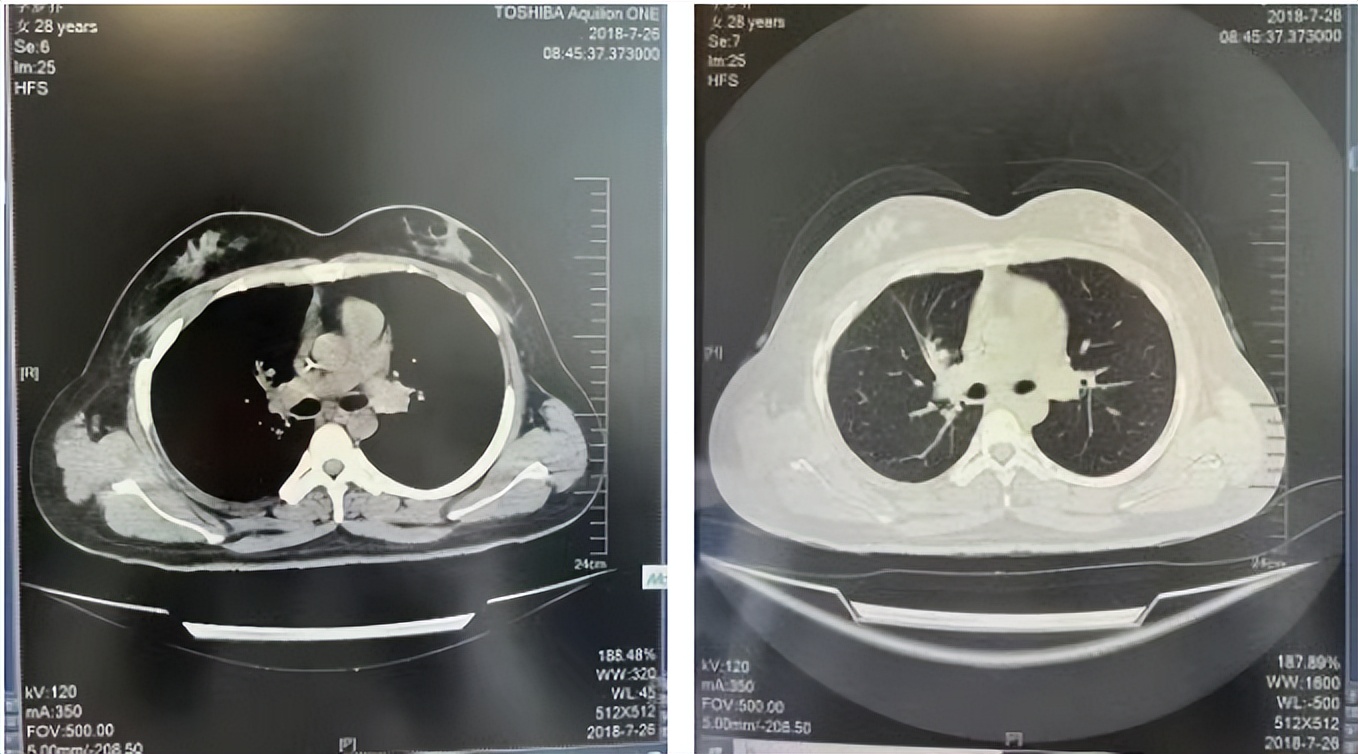

56岁,女性,无吸烟史饮酒史,既往体健。2023年02月患者体检发现肺占位性病变,胸部增强CT:右肺下叶后基底段结节;右侧锁骨上及纵隔内多发淋巴结肿大。PET-CT:右肺下叶周围型肺癌可能性大;1R、2L、3P、4R、4L及7组淋巴结转移可能性大。2023年02月就诊于本院胸外科行超声胃镜下纵隔肿物穿刺活检术,病理:结合免疫组化,符合肺腺癌。行NGS基因检测:EML4:exon20-ALK:exon20融合。PD-L1(克隆号22C3)TPS=55%。

2023年2月20日基线检查

2024年6月复查PR(最佳疗效)

2024年12月复查维持PR

2025年3月复查维持PR